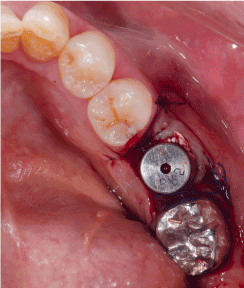

Figure 2a. Oral examination at second stage: buccal concavity and migration of the muco-gingival junction towards the alveolar crest at the implant site is found

Figure 2b. FAST is applied